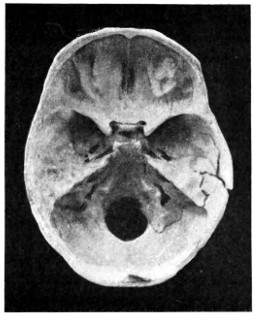

| 50 A and B. The inner aspect of the skull and the same seen on transillumination | 137 |